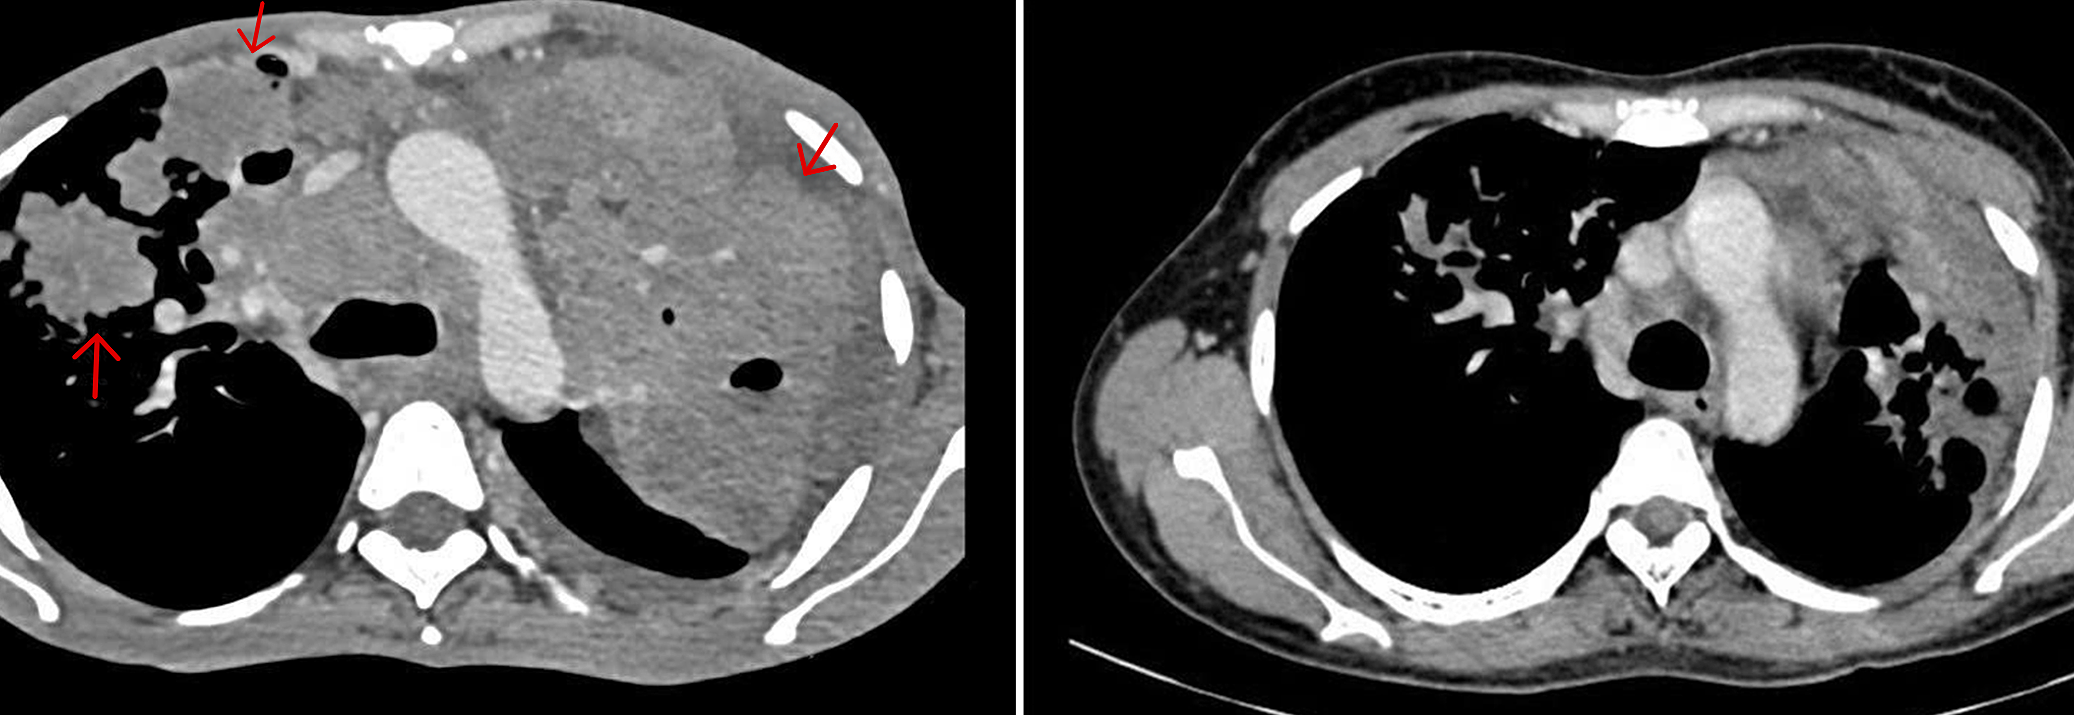

Phuong’s lung CT scan before treatment (left) and after six months (right). Photo: Hospital provided

After 4 immunotherapy injections, Phuong's fever subsided, and she began to gain weight. After the 5th injection, she had gained 17 kg, reaching 48 kg. Her body mass index (BMI) improved from severely underweight to average. Dr. Khiem's clinical examination revealed that the lymph nodes in her neck and armpits had disappeared. A follow-up lung CT scan showed mostly fibrotic lesions, indicating good lung recovery. Having responded well to the immunotherapy, with no further fever or cough, Phuong transitioned to maintenance therapy.